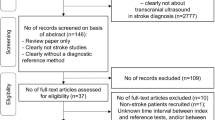

A total of 88 subjects with sufficient initial screenings were obtained at Erlanger Medical Center, of which 50 and 38 were initially enrolled in the LVO and IHC groups, respectively. Three LVO subjects were discontinued (subject either expressed desire to discontinue or was transferred or died before enrollment was completed). An additional 14 LVO and 5 IHC subjects were subsequently excluded due to disqualifying criteria unknown at the time of enrollment. In total, the current analyses included 33 LVO and 33 IHC subjects, with 44 (19 IHC) acquired using the DWL system, and 22 (14 IHC) acquired using the Lucid M1 System. Results of all statistical tests presented herein were identical when performed individually on exams from each system. Patient demographic and occlusion location information is provided in Tables 2 and 3.